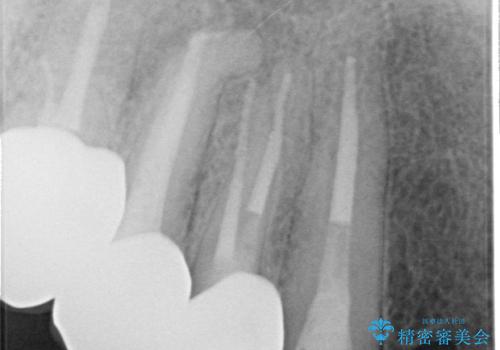

- 歯がない左側でものが咬めず、右側で咬むと歯が痛むので診て欲しいといらっしゃった方の症例です。

根尖病変が認められる歯は再根管治療を行い、歯根が破折していた左上4は抜歯しました。

インプラントは希望されなかったため、左側は1番から7番のロングスパンブリッジによる補綴を行いました。